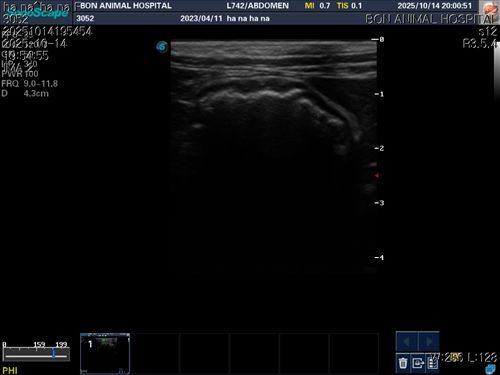

10월 10일 포도를 토해논후로 식욕저하 기력저하가 있어서 동물병원에 방문해서 엑스레이를 찍었는데 우선 지켜보자는 말과 소화제처방과 주사를 맞고 집왔습니다 그 후로도 안먹어서 12일에 동물병원에가서 혈액검사도 하고 수액도 맞았습니다 췌장쪽 수치가 좀 높아서 췌장쪽만 다시 검사했는데 수치는 괜찮았습니다 식욕촉진이랑 소화제처방 받아서 먹이는데 식욕저하도 여전하고 기력이 좀 없고 10일부터 14일까지 대변을 못보고있어서 14일에 병원에 가서 엑스레이랑 초음파를 했는데 장폐색일수도 있다는 말을 들었습니다 초음파상으로는 소장쪽 이물이 의심된다고 하셨어요ㅠ